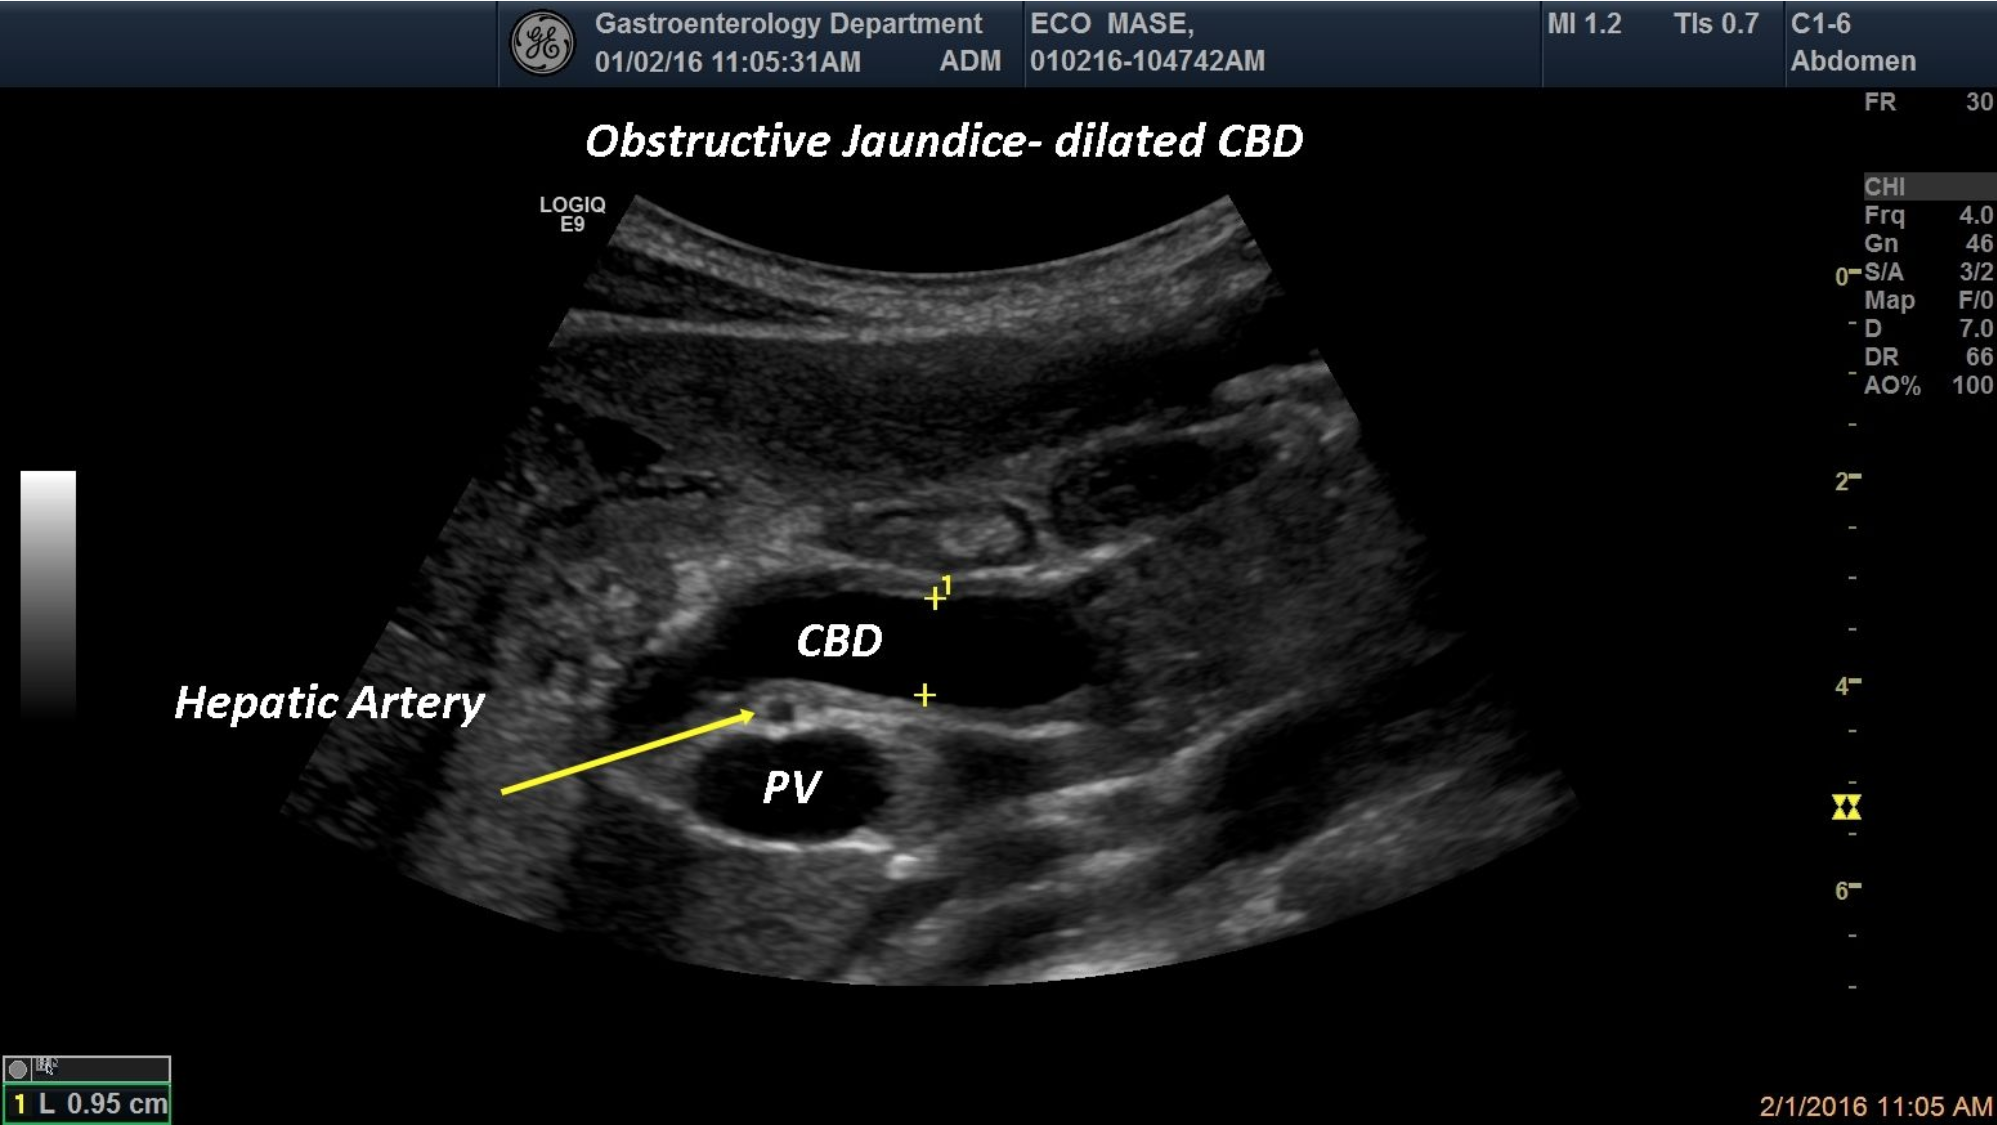

A 76-year-old oncological patient, was referred to our department for obstructive jaundice and fatigue. The standard ultrasound evaluation depicted dilated common bile duct at the hilum level

obstructive jaundice,dilated CBD, hepatic hilum